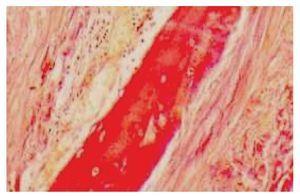

Dos meses después de su egreso, el paciente presentó dolor abdominal de predominio en hipocondrio derecho. Después de realizar ultrasonido de hígado y vías biliares y tomografía computarizada de abdomen, se estableció el diagnóstico de colecistitis aguda alitiásica y calcificación a nivel intestinal por lo que se realizó colecistectomía (Figura 1). Durante el procedimiento se identificó un proceso indurado a nivel intestinal, localizado a 10 cm de la ileostomía a nivel del borde mesentérico. No fue posible hacer el cierre de la ileostomía debido a las múltiples adherencias y al proceso óseo ya descrito. Seis meses después se realizó el cierre de la ileostomía y resección intestinal debido a este proceso óseo, de aproximadamente 10 cm de longitud (Figura 2), misma que se envió a estudio histopatológico que informó inflamación aguda y crónica en ileostomía, congestión vascular y área de metaplasia ósea distrófica asociada a inflamación crónica (Figura 3). El paciente evolucionó satisfactoriamente por lo que fue dado de alta al cuarto día de la cirugía.

¿ Figura 3. Imagen microscópica en la que se observa proceso de osificación a nivel intestinal.